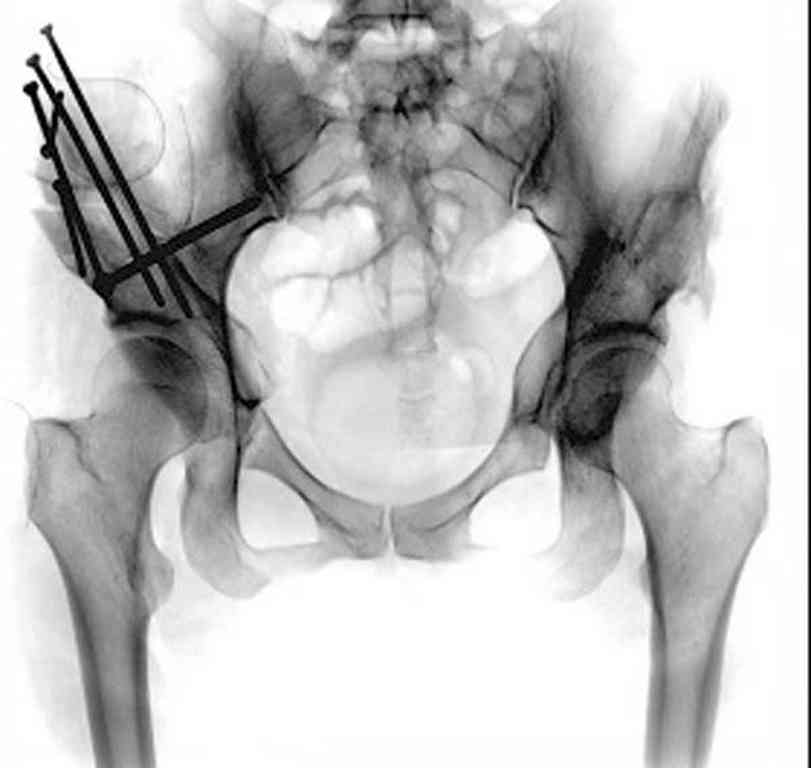

При определении показаний к м/в остеотомии учитываем не только функциональное состояние, но анатомическую форму сустава. Например, при той форме, что на картинке в вашем письме (мелкая впадина,уже не сферичная головка)НИИТО вполне обосновано предлагает ТЭП. Варизирующая остеотомия в "чистом виде" усилит конфликт в опорной зоне сустава. Если очень "настоятельно просит" - экстензия с наружной ротацией по R.Bombelli. То есть на открытом суставе бедро согнуть и ротировать внутрь до покрытия головки впадиной. Сформировать канал через шейку в головку с тем расчетом, что после м/в распила бедро нужно вывести в функциональное положение. Фиксировать 90 град. медиализирующей ортопедической пластиной с клинком. Но выздоровления не обещать, покрытие головки малое, длительного эффекта не будет. Нужна периацетабулярная остеотомия или пластика крыши, но это другая сложность и другая травматичность. Необходимость ТЭП оттянете лет на 10 в лучшем случае. Надо учитывать, что в этом случае ТЭП операция не первая, это увеличивает инфекц. риски и снижает функциональный результат для сустава. Я бы рекомендовал трость с противоположной стороны, ЛФК на приведение, чтобы подрос оссификат крыши и сформировались оссификаты головки. При нормотрофическом типе поражения можно будет провести вальгизирующую остеотомию, эффект которой более длительный или больная за это время найдет возможности приобретения ЭП.

Представляю Р-снимки: обзорная, с отведением и с приведением.

Глубокоуважаемый Абдурашид. Здесь нет снимка с отведением. Если Вы сами сходили в рентгенкабинет и лично отвели пораженную конечность максимально возможно, а также дали максимально возможную внутреннюю ротацию-это одно!!!! Значит у пациентки тяжелейшая приводящая контрактура тазобедренного сустава!! И необходимо разобраться-миогенная или артрогенная? Если же Вы просто назначили указанный снимок и доверили произвести укладку рентгентехнику-это другое!!! Одному богу известно, что она делала, ведь на р-снимке отведения нет!

Все предыдущие корреспонденты предлагают вам достаточно простую вещь-смоделировать предлагаемую Вами операцию (т.е. дать отведение и внутреннюю ротацию) и посмотреть, как изменятся соотношения в суставе. Не обижайтесь, но судя по представлению клинического случая угловые величины, характеризующие пространственные соотношения в тазобедренном суставе, ваши рентгенологи не считают.

Уважаемый Игорь Владимирович. диссертации М М Камоска, и В Е Баскова я нашел, но почему-то не могу открывать, и еще в данном случае имеется дисплазия т/б за счет недоразвития крыши в/впадины да и всей подвздошной кости, маргинального вывиха или латеропозиции головки вследствие лечебных ощибок нет, головка стоит на месте. Р-граммы сделал сам, но почему-то у больной отведение и внутренная ротация стали очень болезненной, и сухожилия приводящих мышц сильно натягивается.(контрактура артро-миогенная).

Глубокоуважаемый Игорь Владимирович! Признаюсь допустил ошибку, из-за напряженности работы и нехватки времени, когда повторно внимательно посмотрел все понял и не успел исправить ошибку до Вашего поста, конечно скошенность крыши в пределах 40гр,часть головки кнаружи линии Омбредана-Перкинса , облитерация дна вертлужной впадины и т.д.-это ДМВБ.